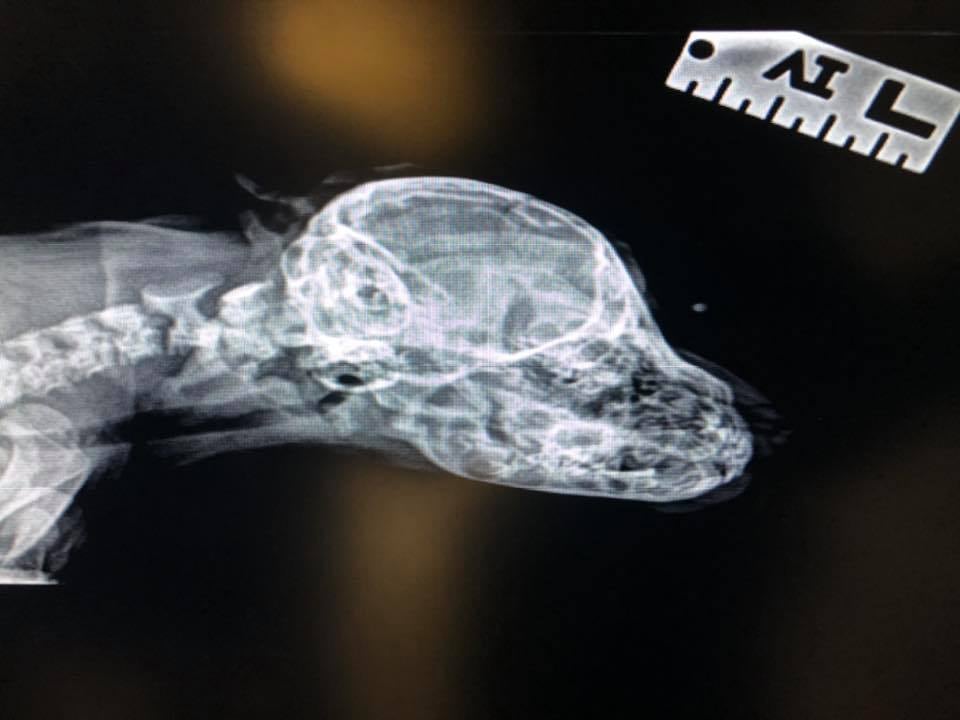

Para determinar si Narwhal podría tener problemas futuros, los médicos veterinarios de la fundación, tomaron una radiografía de su cráneo y encontraron que el “cuerno” está desprovisto de huesos, sólo es piel y pelo que no están conectados a nada así que no podría representar un peligro. Sin embargo, lo mantendrán en observación para asegurarse de que no haya inconvenientes con el posible crecimiento de la protuberancia.